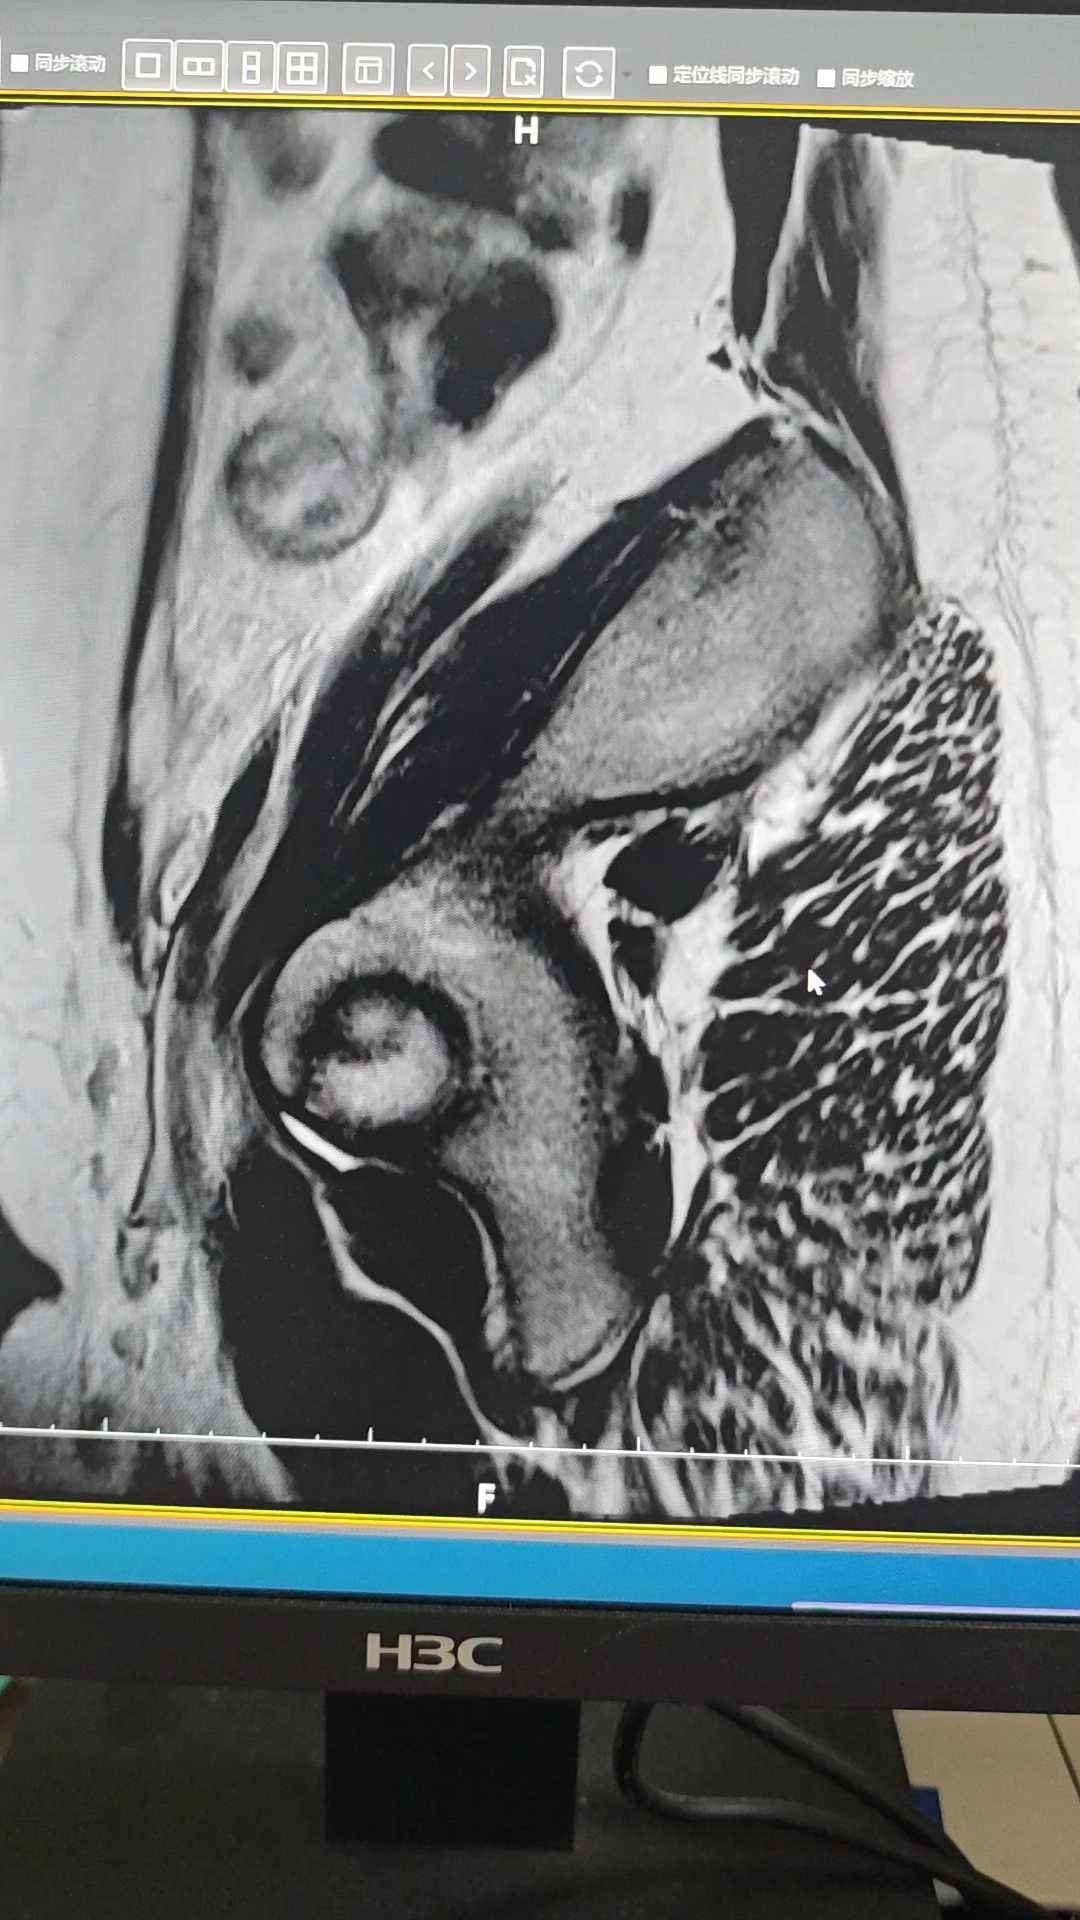

患者,女,13岁5个月,下腹痛4天入院。11岁初潮,月经不规律,量中,无痛经,末次月经2025.5.19。4.25首次出现下腹痛,在诊所输液治疗一天好转。5.31再次出现下腹痛,6.1外院检查子宫附件未见明显异常,血hcg正常。6.2诊所输液无好转。6.3入我院。查体:生命体征平稳,身高170cm,体重:80kg,下腹部压痛明显,腹肌稍紧,无反弹痛。妇科检查:外阴发育正常,未婚产式,肛腹诊检查不满意。盆腔彩超示:盆腔巨大占位性病变伴渗出,考虑来源附件良性囊性病变。盆腔MRI示:盆腔良性囊性病灶。女性肿瘤五项正常。考虑卵巢囊肿蒂扭转,急诊腹腔镜探查,术中见左附件扭转两圈,左侧输卵管囊肿大小约130*80mm呈紫黑色,左卵巢增大55*35mm紫黑色,行左附件切除术。

大家观察正常卵巢和缺血坏死卵巢MRI图像表现